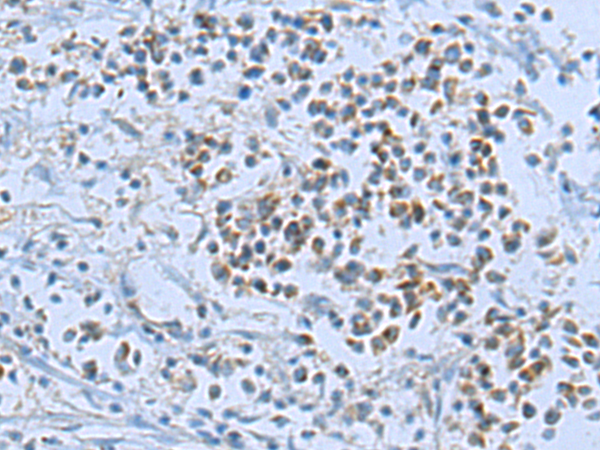

分类: 科研抗体货号: P08707别名: ARHE; Rho8; RhoE; memB应用: IHC反应种属: Human, Mouse, Rat